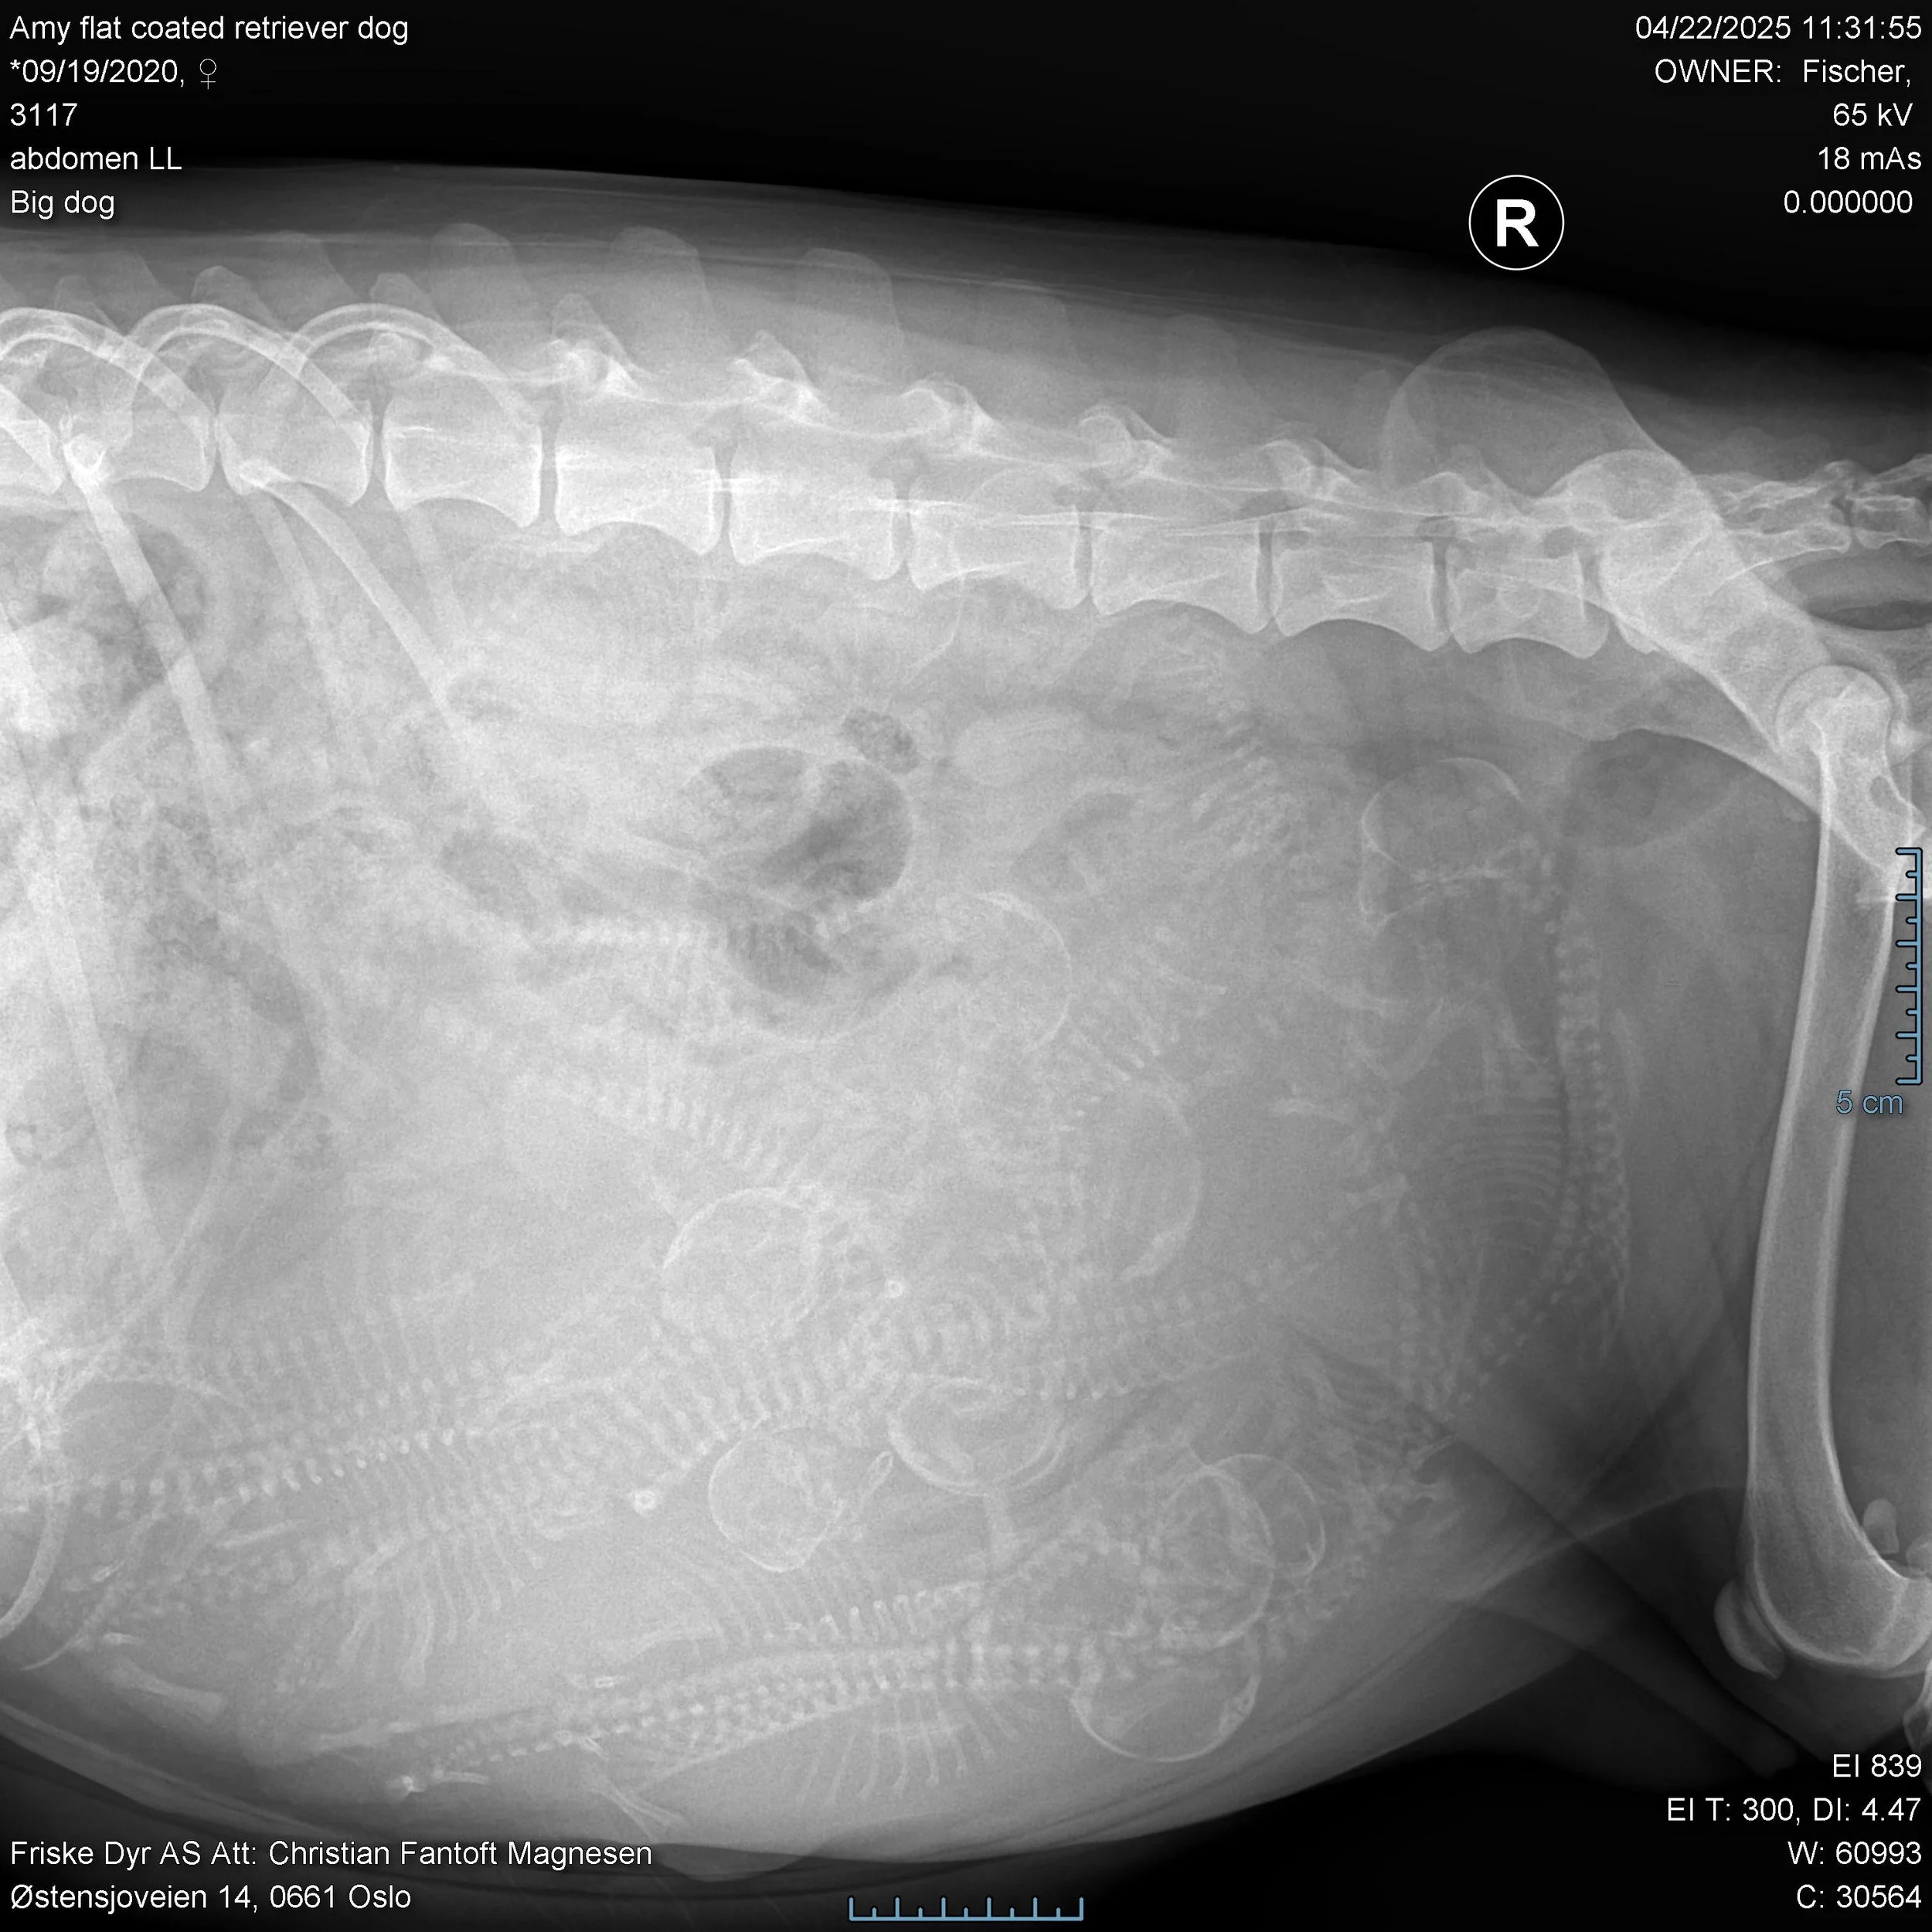

Lill Jacqueline Fischer 22.04.2025 Lill Jacqueline Fischer 22.04.2025 Det kommer et fotballag - med innbyttere Les mer